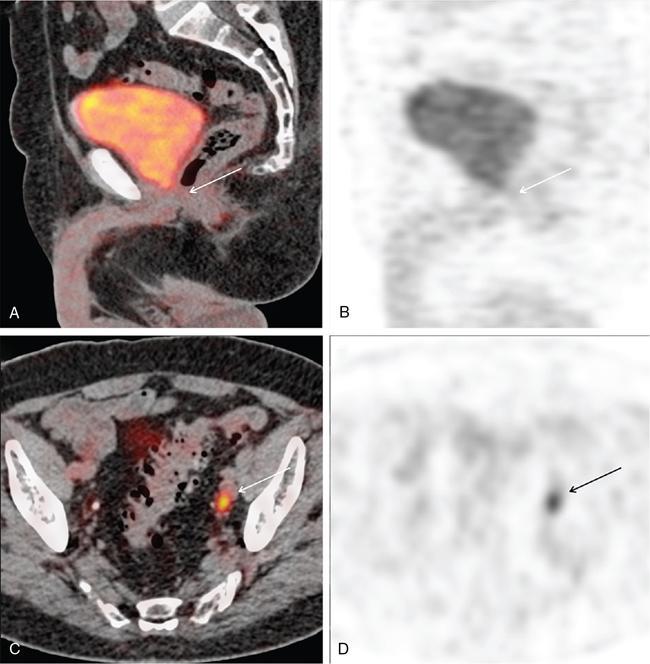

Karthik Ganesan, Disha Lokhandwala, Ujjwal Bhure, Jay Mehta Morphogenesis of the male genitourinary system is governed by the coherent interaction of three units, namely the Wolffian duct, urogenital sinus and foetal gonads. The Wolffian ducts are the embryonic precursors of the male internal genitalia, arising in the anterior intermediate mesoderm at 4 weeks of gestation. They elongate as a cord of cells that caudally extend to the urogenital sinus. Between 5 and 8 weeks of gestation, the urorectal septum divides the cloaca into a ventral compartment, which forms the urogenital sinus, and a dorsal compartment, which forms the rectum. The gonads form as epithelial thickenings on the ventromedial surface of the mesonephros and produce testosterone at 8 weeks of gestation, reaching a peak at 10–15 weeks. Under the effect of testosterone produced by the foetal testis, the prostate anlage forms at the tenth week of gestation. Precursor of the anlage begins with proliferation of solid epithelial buds from the epithelium of the urogenital septum into the adjoining mesenchyme in response to interaction of 5α-dihydrotestosterone with mesenchymal androgen receptors. As growth progresses, solid cords of epithelial cells are formed, growing into the mesenchyme in a specific three-dimensional arrangement (establishes the lobar divisions of the prostate gland). These solid cords develop a central lumen at birth and are lined by a layer of flat basal epithelium and a luminal layer of tall columnar secretory epithelium. Mesenchymal component forms the stroma, which has a large proportion of smooth muscle. Postnatally, the epithelial cords continue to arborize till puberty without any change in volume or glandular architecture. Although the foetal prostate has been described to have a histologically distinct peripheral zone (PZ) as early as 12 weeks of gestation, the mature zonal anatomy develops in concordance with the androgen surge at puberty. The most commonly utilized ultrasonographic technique for the evaluation of the prostate is via a suprapubic approach. The abdominal transducers used in this approach are relatively low frequency and while it offers the advantage of greater depth of penetration without intracavitary probe insertion; however, it does not depict the zonal anatomy and its chief application lies in volume estimation. Hence, transrectal ultrasonography (TRUS) completely outweighs the transabdominal approach in terms of depicting zonal anatomy, visualizing and localizing small lesions, demonstrating vascularity and performing biopsies. TRUS is performed using high frequency transducers (5–7.5 MHz) to optimize soft tissue resolution. An enema is administered 1 h prior to the examination to clear the field of insonation. Patient is positioned in left lateral decubitus, with knees bent toward the chest and ideally a digital rectal examination (DRE) is conducted prior to probe insertion. The transducer is first draped with a sterile barrier and lubricated, After insertion, the barrier is filled with 40–50 cc of water, making sure that no air enters. On completion, water is aspirated and the probe is withdrawn. The gland is initially scanned in the axial plane from the base to the apex, beginning at the level of the seminal vesicles, and the probe is gradually withdrawn to view the entire glandular parenchyma in axial sections up to its caudal aspect. This approach allows a cursory evaluation of glandular symmetry as both halves of the prostate can be evaluated simultaneously. Subsequently, sagittal views are acquired by rotating the probe across the transverse span of the gland, demonstrating the seminal vesicles, midline gland (visualizing both the apex and the base), with sequential scanning up to the contralateral margin of the gland. Sonographically, the prostatic capsule is seen as a smooth well-delineated, hyperechoic structure. With the newer ultrasound systems, the zonal anatomy can be delineated by TRUS; PZ appears echogenic relative to the central zone (CZ) and the transition zone (TZ), which are hypoechoic in juxtaposition (Fig. 11.12.1). Anterolaterally, the preprostatic venous plexuses are seen as anechoic tubular structures with intervening echogenic preprostatic fatty tissue. Glandular volume is estimated using an ellipsoid formula by obtaining the maximum anteroposterior, superoinferior and transverse dimensions and multiplying their product by π/6. Colour Doppler imaging is utilized to illustrate vascularity, as majority of the normal prostatic tissue (excluding the neurovascular bundles [NVBs] and pericapsular and periurethral regions) has symmetrical but sparse flow and an increased microvessel density raises the suspicion of prostatic carcinoma. However, the appearances of prostatic carcinoma can be variable on colour Doppler imaging, ranging from focal increase in vascularity around a nodule to an asymmetric increase in size and number of vessels on the affected side and conventional Doppler has found to elevate specificity by about 5%–10%. Additionally, Doppler imaging has also demonstrated some utility in distinguishing fibrotic tissue from local recurrence. However, vessels supplying cancerous tissue are of the order of 10–50 μm, which is well below the 1-mm resolution limit of conventional Doppler techniques. Contrast-enhanced colour Doppler imaging overcomes this limitation and facilitates imaging of microvessels, using intravenously administered microbubbles (less than 10 μm diameter) of an inert gas (sulphur hexafluoride) with a lipid or galactose shell, allowing quantification of blood flow in the cancerous microvessels. Additionally, these microbubbles act as vascular tracers and by monitoring the passage of a bolus injection through the tissue of interest, time–intensity curves are created. This permits the formulation of functional indices, including bolus arrival time, time to peak intensity, area under the curve and wash-in/wash-out curves. These indices can further extrapolate functional images, on a pixel-by-pixel basis, overlaid on grey-scale images. Quantitative methods to demonstrate perfusion are based on the destruction of microbubbles by high-power ultrasound pulses, and then observing the rate of microbubble replenishment in the field of interest to calculate flow rate. Halpern et al. utilized contrast-enhanced ultrasound and intermittent harmonic imaging with power Doppler, and exhibited an increment in sensitivity from 38% to 65% with a specificity of 80% in prostate cancer detection. Cadence contrast pulse sequencing (CPS) is a low-power multipulse imaging technique utilizing pulses with variable amplitudes and phases followed by a summation of the resulting echoes, permitting tissue suppression, allowing detection of even a small amount of contrast agents retained in the tissues. Real time elastosonography evaluates and quantifies tissue stiffness (Young’s modulus) by measuring strain under an applied stress (transducer compression) and maps areas of variable stiffness in colour-coded and grey-scale images simultaneously and shows potential in improving prostatic carcinoma detection. In a study comparing elastography and T2-weighted (T2-w) endorectal magnetic resonance imaging (MRI), similar sensitivity rates and negative predictive values (NPVs) were attained in the detection of prostatic carcinoma. Prostate gland is an inverted cone-shaped subperitoneal retropubic gland, with its base located rostrally and apex located caudally. The base is attached to the bladder neck and the apex sits on the urogenital diaphragm and abuts the medial surface of the levator ani muscles, namely the pubourethralis portion, which is separated from the inferolateral surfaces of the gland on either side by the prostatic venous plexus. Normal prostate gland measures approximately 4 × 3 × 3 cm, 15–20 g in weight, with a median volume of 11.5 mL (range, 1.6–20.6) in patients between 21 and 25 years and a median volume of 39.6 mL (range, 13–169.8) in patients between 38 and 83 years. The first comprehensive publication describing the anatomical subdivision of the prostate gland was in 1912 by Lowsley, based entirely on the embryonic glandular morphology at a series of gestational age groups. The budding prostatic ducts were seen to proliferate in five distinct clusters from the primitive urogenital sinus, which formed the basis of its lobar subdivision. It was divided into a ventral lobe (anterior to the urethra), two lateral lobes (lateral to the ejaculatory ducts), a posterior lobe (between the ejaculatory ducts) and a middle lobe (above the ejaculatory ducts). This classification had several shortcomings, the foremost being inclusion of only the embryonic prostate during its conception. Frank highlighted these aspects in 1953 and stated that no definite lobar boundaries exist in the adult prostate and further criticized the exclusion of periurethral glands (inner gland), identifying them as the sole site of origin of benign prostatic hyperplasia (BPH). The chief drawback of all research prior to 1968 was the lack of a concrete histological basis to support the seemingly arbitrary subdivision. McNeal was the first to ascertain histological heterogeneity within the glandular tissue and used it as the basis of his well-acclaimed prostatic zonal classification. The zonal anatomy of the prostate gland conceived by McNeal divided the gland into four distinct zones, namely the TZ, PZ, anterior fibromuscular zone (AFMZ) and the CZ (Fig. 11.12.2). McNeal used the plane of the distal urethra to describe the zonal relationships and divide the gland broadly into three parts, namely the base, midgland and the apex (Fig. 11.12.3). The improved understanding of the prostate anatomy coincided with the development of MRI in the late 1980s, which could depict the zonal anatomy, unlike ultrasonography (USG) or computed tomography (CT). Patterns of ductal growth and radiation from the prostatic urethra form the basis of the zonal anatomy of the gland. Ducts arising from the proximal urethral segment grow towards the urinary bladder. Tiny ducts which are confined by the preprostatic sphincter form the small periurethral gland, whereas ducts which develop distal to the lower border of the preprostatic sphincter extend laterally and then anteromedially to form the TZ. Ducts arising from the verumontanum in the vicinity of the ejaculatory duct orifices and are directed towards the base along the course of the ejaculatory ducts form the CZ, whereas ducts which arise from the lateral recess of the posterior urethral wall of the verumontanum and distal urethra radiate laterally to form the PZ and rostrally posterior to the CZ at the base of the gland. PZ is the dominant glandular component of the prostate gland comprising approximately 70% of the glandular tissue. On T2-w images, the normal PZ has a high T2 signal intensity (SI), owing to the abundant ductal and acinar elements with sparsely interwoven smooth muscle, and can broadly divided into three sections as per the sector map in Prostate Imaging Reporting and Data System Version 2.1 (PI-RADS v2.1), namely posterior medial, posterior lateral and anterior sections (Fig. 11.12.4). At the apex, the anterior sections have a horn-like morphology, curving anteromedially, to nearly encircle the urethra and abut the AFMZ. At the midgland level, the PZ comprises the posterior, both lateral and the anterolateral parts of the gland. At the base, the PZ is located posterior and superior to the CZ and TZ. CZ is an ovoid-shaped structure at the base of the gland, comprising approximately 25% of the glandular tissue, with its apex located at the verumontanum, surrounding the ejaculatory ducts. Beyond age 35, volume of the CZ starts to gradually diminish, as well as the CZ is compressed by the enlarged TZ. In the initial MR studies of prostate, the CZ could not be easily delineated from the TZ. Vargas et al. demonstrated in a population with a mean age of 60 years undergoing MR for prostate cancer assessment, the CZ was visible in 81%–84% of patients. Hansford et al. identified the CZ in 92%–93% of patients on T2-w images and 78%–88% of patients on apparent diffusion coefficient (ADC) maps. Histologically, substantial differences exist between the CZ and PZ, which reflect in the differential appearance on T2-w imaging. These differences are probably attributable to the differential origin, as the CZ is derived from the Wolffian duct, and the PZ and TZ are derived from the urogenital sinus. In the CZ, the acini appear larger and more irregular, with numerous epithelial covered ridges or septa project from the walls of the acini into the lumen, forming a characteristic Roman bridge architecture and intraglandular lacuna, with a prominent basal layer, crowded epithelial cells with granular eosinophilic cytoplasm, decreased luminal fluid and compact stroma. PI-RADS v2 has discouraged the use of the term central gland, as it is not reflective of zonal anatomy or reported on pathologic specimens. CZ demonstrates homogeneously low signal on the T2-w images and ADC maps and can, therefore, mimic prostate cancers. CZ is best identified on the coronal plane T2-w images paralleling the plane of the distal urethra, and appears as a symmetric paramedic paired structures surrounding the ejaculatory ducts from the base of the gland to the verumontanum (Fig. 11.12.5). TZ comprises approximately 5% of the glandular tissue of the prostate. On T2-w images, the TZ normally appears as a homogeneously hypointense structure surrounding the proximal urethra at the base and the midgland level; however, it can also demonstrate inconsistent SI, depending on the relative proportion of glandular and stromal elements (Fig. 11.12.6). Glandular hyperplasia produces higher SI (dominance of acinar elements and secretions), while stromal hyperplasia exhibits lower SI (dominance of muscular and fibrous elements). The TZ is easily demarcated from the PZ by a thick homogeneously low T2 signal surgical capsule, which becomes pronounced in BPH. With increasing age, the TZ demonstrates variegated signal on the T2-w images and ADC maps, due to differential growth of the stromal and glandular elements. AFMZ is a nonglandular muscular tissue that drapes the anterior surface of the gland, superiorly blending into the smooth muscles of the bladder neck and inferiorly extending to the prostatic urethra at the glandular apex. AFMZ is comprised of smooth muscles, which blends with the smooth muscle fibres surrounding the urethra, and rostrally merges with the bladder neck and preprostatic sphincter. High smooth muscle content of the AFMZ is responsible for the MR signature, where in it appears markedly hypointense on the T2-w images and ADC maps, and hypoenhances on the multiphase contrast series (Fig. 11.12.7). With the advancing age, temporal reduction in the size of the AFMZ is noted due to the compressive effects of the BPH. Capsule surrounds the prostate gland, anteriorly merging with the AFMZ anteriorly. Two discrete defects are identified in the prostate capsule, at the base of gland where the ejaculatory ducts enter the prostate and at the apex where in the stroma blends with the sphincter. The capsule is perforated along the anterolateral aspect by multiple vessels and nerves. The capsule appears as a thin dark rim surrounding the gland on the T2-w images and may reveal delayed enhancement on the postcontrast images (Fig. 11.12.8). Primary goal of radical prostatectomy (RP) is to achieve oncologic efficacy, both in terms of short-term and long-term clinical outcomes. However, as the majority of prostate cancers have an indolent clinical course, preservation of function in terms of continence and potency is equally important, and the key to this is a keen understanding of the fascial anatomy and neuroanatomy of the prostate gland. Fascial anatomy of the prostate gland is anatomically complex and poorly understood, and a thorough understanding of the interfacial planes is crucial to avoid mechanical or thermal injury to the NVBs. Periprostatic fascia comprises of a condensation of layers of connective tissue that encapsulate the gland and suspend it from anterior pelvic wall via puboprostatic ligaments. Laterally, the visceral and parietal endopelvic fascial layers fuse to form the fascial tendinous arch. Periprostatic fascia covers the prostate gland and capsule, comprises of two fascial layers, including an inner layer (prostatic fascia) and an outer layer (levator ani fascia), with thin interfascial planes separating these fascia from one another and the prostate capsule. Posteriorly, a continuous fascial layer known as Denonvilliers’ fascia covers the prostate and seminal vesicles. Distribution of periprostatic nerves is highly variable, with growing evidence of nerves both along the dorsolateral and ventrolateral surfaces of the prostate gland. Most of the periprostatic nerves are found posterolaterally; however, a significant portion of the nerves are located ventrally as seen by Eichelberg et al. (21.5%–28.5%) and Lee et al. (19.9%–22.8%). Although anatomic studies have confirmed the presence of ventrolateral periprostatic nerves, the exact clinical importance and functionality of these nerve fibres has not been proven. The cavernous nerves are situated posterolaterally and are the basis of nerve-sparing RP procedure proposed by Walsh and Donker. Unlike the initial theory of Walsh and Donker, few papers have proposed that the nerves are diffusely scattered along the surface of the gland in the form of a curtain or spray-like arrangement without clear bundle formation. Kourambas et al. assessed the precise relationship of the NVBs and cavernous nerves to Denonvilliers’ fascia and proposed that the nerves were not restricted posterolaterally, but were rather diffusely scattered within the fascia extending up to the midline (Lunacek et al., Takenaka et al.). On the basis of more diffuse arrangement of the periprostatic nerves, surgical techniques have been modified, resulting in a more anterior dissection called the ‘curtain dissection technique’ or alternatively a ‘superveil’ technique to preserve the NVBs within the lateral prostatic fascia. The NVB lies within areolar connective tissue surrounding the gland, which separates the capsule from the periprostatic fascia and provides a plane of dissection during nerve-sparing prostatectomy. Prostate gland is supplied and drained by periprostatic vessels, which also supply and drain the penis. Arterial supply of the gland is highly variable and is typically from branches of the internal pudendal artery, which course inferior to the gland prior to supplying the penile cavernosal tissue. Off late, these vessels have gained prominence in radiation-induced erectile dysfunction (ED) (potential vasculopathy), which have led to the development of newer vessel-sparing radiotherapy techniques. Further, with the advent of prostate arterial embolization in benign prostatic hypertrophy (BPH), the vascular supply of the gland is becoming increasingly vital to understand. Gland drains into the obturator, internal iliac, external iliac, common iliac and presacral lymph nodes. Dorsal venous complex is identified immediately ventral to the gland and also drains the penis. Periprostatic nodes are uncommon, are usually discovered near the base of the gland, and are only occasionally seen on MRI. Urethra is the principal anatomic reference point in the prostate gland. Urethra can be divided into a proximal segment and a distal segment, the point of differentiation being located at the verumontanum wherein the urethra makes an approximately 35-degree angulation. The angulation is highly variable and is further affected by the growth of the TZ. On MRI, the distal segment is more conspicuous vis-à-vis the proximal segment and appears a hyperintense core surrounded by a low signal rim on T2-w images. Preprostatic sphincter encases the proximal urethra from the base of the gland to the base of the verumontanum and merges with the AFMZ anteriorly. Verumontanum appears hyperintense on the T2-w images, lies within the distal urethral segment, beyond which the distal urethral segment is partially encircled by striated muscles which blend with the external sphincter beyond the apex of the gland. External sphincter is located distal to the apex is incomplete posteriorly and is anchored into the PZ and surrounds the membranous urethra. Damage to the external sphincter during RP or transurethral resection of the prostate (TURP) may lead to urinary incontinence. Seminal vesicles are paired structures identified posterosuperior to the base of the prostate gland, which appear as convoluted fluid-filled structures. Due to the high fluid content within the normal seminal vesicles, these structures appear as paired structures with intermediate signal walls surrounding a hyperintense core on T2-w images (Fig. 11.12.9). Vas deferens are paired structures located rostral to the base of the gland and anteromedial to the seminal vesicles and appear as cord-like structures with variable signal on the T2-w images. Duct of the seminal vesicle and vas deferens unite in the posterior aspect of the base of the gland to form the ejaculatory duct, which courses caudally to the verumontanum along the plane of the distal urethra, and drain into the orifices in the midconvexity of the verumontanum. Prostate-specific antigen (PSA) is a serine protease, secreted by epithelial cells of the prostate gland and has been found in normal, benign and malignant prostatic tissues. Traces of PSA have also been isolated from endometrial tissue, breast tissue, adrenal neoplasms and renal cell carcinomas; however, for all clinical purposes, PSA is considered as an organ-specific biomarker. Papsidero first demonstrated and quantified serum PSA, which steered the epoch of prostate cancer screening and early detection of prostatic carcinoma. Subsequent studies showed that PSA screening often led to overdiagnosis of low-grade prostate cancers, with no survival difference between the PSA screened and nonscreened groups. Additionally, PSA levels were found to be elevated in a spectrum of prostatic pathologies apart from carcinoma, including prostatitis and benign hyperplasia. The likelihood of overdiagnosis coupled with the lack of specificity set grounds for the longstanding PSA controversy. Did the benefits of screening outweigh the risks of overtreatment? To elevate the specificity of serum PSA testing, a plethora of indices were devised, including free PSA and total PSA, free-to-total PSA (f/t PSA) ratio, age-specific PSA, PSA velocity (PSA-V) and PSA density (PSAD). Serum PSA exists in three forms; the major form (approximately 75%) is bound to alpha-1-antichymotrypsin, followed by free PSA (constituting 5%–50% of serum PSA). The third form (PSA bound to alpha-2-macroglobulin) is not clinically relevant and cannot be detected by any commercial test. A study by Stenman et al. established that a higher proportion of bound PSA and hence a lower ratio of f/t PSA is associated with prostate cancer. Conversely, free PSA can be utilized during follow-up for men with an initial negative biopsy result, wherein declining free PSA with a persistently elevated total PSA would raise suspicion of a neoplastic aetiology. As per the ACS guidelines (Table 11.12.1) for early detection of prostate cancer, men with a 10-year life expectancy or higher should have the opportunity to make an informed (regarding benefits, risks and uncertainties associated with PSA screening) decision for serum PSA testing, with or without DRE. For those who choose to undergo PSA screening, subsequent screening interval is determined on the basis of baseline PSA value. For values below 2.5 ng/mL, screening interval can be extended to 2 years and for PSA between 2.5 ng/mL and 4 ng/mL, an individualized approach is adopted following risk assessment to recommend either further referral or screening on a yearly basis. A PSA level of 4 ng/mL or higher warrants referral for further evaluation or biopsy, for men at average risk for prostate cancer. Although age-specific PSA (Table 11.12.2) is not a component of the ACS guidelines, it is considered as a beneficial parameter in determining the need for biopsy. As there is an expected rise in PSA values with age, setting a lower cut-off value for younger men would increase the sensitivity of detecting organ confined cancers and a higher value in older men would increase specificity. aThere is no proven rationale for using a single PSA-V threshold value. PSA screening guidelines for treated localized prostate cancers are variable and the definition of biochemical (PSA) recurrence remains debatable. Due to this inconsistency, the Prostate Cancer Guidelines Update Panel recommended a standard definition for biochemical recurrence (BCR) after RP and set a cut-off serum PSA (acquired between 6 weeks and 3 months of surgery) of 0.2 ng/mL or greater, along with a second confirmatory PSA. While there is a significant fall in PSA values after RP and a single raised PSA is sufficient to raise suspicion of recurrence, postradiotherapy recurrence requires a rising trend rather than a single cut-off value. The ASTRO Consensus Panel defined postradiotherapy prostate cancer recurrence as three consecutive raises in PSA values after a baseline has been reached. A hiatus in this definition was that no specific time interval between consecutive increases in PSA was determined. In addition to its utility as a screening tool, PSA is also a good prognosticator when used in conjunction with biopsy Gleason score and clinical T-stage, and several pretreatment prostate cancer risk stratification systems are based on these indices. D’Amico et al. proposed a three-group risk stratification system in 1998, which categorized nonmetastatic (M0) carcinomas as low risk, intermediate risk and high risk. Low-risk prostate cancer was defined as 1992 AJCC T1/T2a, PSA ≤10 ng/mL and Gleason score ≤6. Intermediate-risk prostate cancer was defined as 1992 AJCC T2b, and/or PSA 10–20 ng/mL and/or Gleason 7 disease. High-risk disease included any one of the following: 1992 AJCC ≥T2c, PSA >20 ng/mL or Gleason 8–10 disease. In 2001, the GUROC published the results of a consensus meeting which categorized the groups as follows: low risk – 1997 AJCC T1–T2a, PSA ≤10 ng/mL and Gleason ≤6; intermediate risk – 1997 AJCC T1–T2, PSA ≤20 ng/mL and Gleason ≤7 not otherwise low risk and high risk – 1997 AJCC T3–T4 or PSA >20 ng/mL or Gleason 8–10. In due course, newer classification systems have been developed (Table 11.12.3), including the National Comprehensive Cancer Network (NCCN, USA), National Institute for Health and Clinical Excellence (NICE, UK), European Society of Medical Oncology (ESMO), American Urological Association (AUA) and the European Association of Urology (EAU). The NCCN guidelines also incorporate very low-risk (T1c, and Gleason score ≤6, PSA ≤10 ng/mL, <3 positive biopsy cores each ≤50% involved and PSAD of <0.15 ng/mL/g) and very high-risk (T3b–T4) categories. AUA, American Urological Association; EAU, European Association of Urology; GUROC, Genitourinary Radiation Oncologists of Canada; NICE, National Institute for Health and Clinical Excellence; CAPSURE, Cancer of the Prostate Strategic Urologic Research Endeavour; NCCN, National Comprehensive Cancer Network; ESMO, European Association of Urology; T, T-stage; GS, Gleason score; PSA, prostate-specific antigen. Note: Use of the 1997 TNM staging system (T2a one lobe involvement, T2b two lobes involvement, no T2c category). PSA, DRE and TRUS form the diagnostic triad for prostatic carcinoma. It has been well established that manipulations of the prostate gland, including prostatic massage, cystoscopy and perineal biopsy cause a potential increase in serum PSA levels. This raised the question of TRUS affecting PSA levels and it was found to cause a very small rise in PSA only in patients with prostatitis. The effect of DRE on serum PSA levels is also controversial, while some studies found a transient increase in PSA, others found no significant rise in PSA levels after DRE. Therefore, it is advisable to obtain blood samples for PSA testing either prior to DRE and TRUS or after at least 7 days. PSA-V refers to the change in PSA over time using serial measurements. Ideally, at least three consecutive measurements over at least 18–24 months should be used. Carter et al. first defined PSA-V and found that a value of 0.75 ng/mL per year or greater was indicative of carcinoma with a high sensitivity and specificity. Consequently, several studies disproved a definite relationship between PSA-V and prostate cancer, stating that there was no rationale behind a single threshold value for PSA-V. Further, it was found that calculating PSA-V was arduous and while elevated PSA values on serial examinations should raise alarm, there was no added benefit of formally calculating PSA-V. As per NCCN guidelines, the PSA-V cut-off should be based on the initial PSA value with a PSA-V of 0.35 ng/mL/y, when the PSA is ≤2.5 ng/mL and 0.75 ng/mL/y, when the PSA is 4–10 ng/mL PSAD was developed in order to correlate prostate volume and PSA values. The basis of PSAD was that cancer cells produce more PSA per unit volume than normal cells. It is calculated as PSA value divided by the prostate volume as determined by TRUS. This reliance on TRUS leads to interobserver variability and hence PSAD values would differ with the performing sonologist. The chief utility of PSAD is in the diagnostic grey zone of PSA values between 4 and 10 ng/mL and the most commonly used cut-off value is 0.15 ng/mL/cc. However, more recent studies have shown that a value of 0.08 ng/mL/cc has an NPV of 95% in predicting prostate cancer. Additionally, PSAD in conjunction with MRI (PI-RADS score) has proved to be a reliable prognosticator for Gleason score upgrading. The most significant application being avoiding unnecessary biopsies as PI-RADS scores of 1–3 along with PSAD values <0.15 ng/mL/cc showed no Gleason score upgrading on repeat biopsies. In summary, most guidelines recommend shared decision-making for screening of prostate cancer. Limited testing should be conducted in men with low PSA values and a lower life expectancy. The aim should be to overcome challenges posed by the inherent nonspecific nature of serum PSA and reduce superfluous testing, unwarranted biopsies and overdiagnosis. Reliance on parameters like PSA-V that do not have a proven scientific basis is avoidable. Whereas applications of PSA like PSAD along with MRI can greatly reduce patient burden by avoiding follow-up biopsies. Lastly, PSA has no role in assignment of a PI-RADS category, which is based on multiparametric MRI (mpMRI) findings alone. Several ‘novel biomarkers’ are now being developed which are more specific in detecting high-grade prostatic carcinomas. Other human kallikrein proteins have been identified, as prostate cancer biomarkers, of which, human kallikrein 2 (hK2) has shown a high specificity. While hK2 and PSA have an overlapping primary structure, malignant cells express hK2 to a higher degree than benign epithelial cells, particularly in aggressive cancers. Engrailed-2 (EN2) is an HOX gene family transcription factor seen exclusively in malignant prostate tissue, with a reported sensitivity and specificity of 66% and 88%, respectively. Annexin A3 is a calcium-binding protein measured in urine samples following prostatic massage, potentially reducing unnecessary biopsy in men with a PSA of 2–10 ng/mL. However, extensive prospective evaluation of these biomarkers is necessary to replace PSA testing in clinical practice. Positron emission tomography (PET)/CT has evolved over the last two decades to make a paradigm shift in the field of imaging, moving from morphological imaging to molecular level and completely changing the approach to how we view the disease. Though the main workhorse tracer in the field of PET/CT is 18-fluorine-fluorodeoxyglucose (18F-FDG), it has limitations with regard to prostate cancer, especially in indolent or well-differentiated ones. However, that void has been filled up by the new kid on the block and that is prostate-specific membrane antigen (PSMA)-based radiotracer. PSMA is a type II transmembrane protein with intracellular (19 amino acids), transmembrane (24 amino acids) and extracellular (707 amino acids) domains, which functions biochemically as a glutamate carboxypeptidase. After a ligand binds to PSMA, internalization occurs and it is either retained in lysosomal compartments or released into the cytoplasm. PSMA expression and localization in the normal human prostate is associated with cytoplasm and apical side of the epithelium surrounding prostatic ducts but not basal epithelium and neuroendocrine or stromal cells. Neoplastic transformation of prostate tissue results in the transfer of PSMA from the apical membrane to the luminal surface of the ducts. PSMA is an ideal target for molecular imaging of prostate cancer as its expression is significantly upregulated in prostatic carcinoma cells compared to benign prostatic tissue, in density (100 to 1000 times) as well as activity (8 to 10 times). PSMA expression increases with increase in Gleason score, stage and grade of tumour, with further increased expression with transition to androgen-independent/castration-resistant prostate cancer. PSMA-binding analogues, because of their high sensitivity and specificity, possess precise imaging characteristics required for critical decisions in the management of prostate cancer (PCa). The most commonly used PSMA radiotracer is 68Gallium-PSMA-11, followed by 18F-PSMA. The availability of 18F-labelled PSMA radiopharmaceutical has helped to advance the reach of PSMA PET imaging to wider locations owing to higher available amount of the radiotracer due to its production from a cyclotron, compared to 68Ga-PSMA which is eluted from individual in-house generator. Additional benefit is accrued with excellent image quality owing to optimized radiotracer doses, higher imaging statistics and favourable decay properties of 18F radioisotope. The normal physiological biodistribution of PSMA-based radiotracers is seen in lacrimal and salivary glands, liver, spleen, kidneys and intestine. Physiological activity is also seen in celiac and cervicothoracic ganglia. Unbound PSMA radiotracer is excreted by the kidneys into the urinary bladder. PSMA PET/CT has established roles of varying degrees in the imaging of different aspects of prostate cancer including primary diagnosis, staging, BCR after primary prostate cancer treatment (prostatectomy), identification and significance of oligometastasis, restaging and treatment response assessment and monitoring. PSMA PET/CT is useful at the stage of diagnosis in that subset of patients with tumour-negative biopsy samples, by contributing the useful molecular information to mpMRI, helping to precisely delineate suspicious lesions for targeted biopsies. In intermediate-risk to high-risk primary prostate cancer patients, PSMA-based imaging has shown improvement in detection of metastatic disease compared to the CT and mpMRI, which has led to reduced demand and dependence on additional cross-sectional imaging or bone scintigraphy. Furthermore, PSMA PET/CT has also established its clear advantage over conventional imaging in patients with biochemically recurrent prostate cancer with improved and increased detection of metastatic sites even at low serum PSA values. As it happens in cancer, biopsy is the standard of diagnosis and likewise in PCa, it is the multicore biopsy, which is the gold standard. However, because of its size, location, approach and sensitive and delicate nature, yield and accuracy can often be restricted, especially in inexperienced hands. The diagnostic yield of biopsy can go down as low as 40% and false negative (FN) rate can climb as high as 25%–30%. PSMA overexpression follows high-grade PCa cells and increases with Gleason score. In normal prostate tissue, PSMA to PSA ratio is about 1, which decreases in BPH, increases in primary PCa cells, further increases with intratumoural angiogenesis, higher in metastatic lesions than in primary PCa cells and further upregulated in castration-resistant situation. In a study by Litwin and Tan in 2017, the FN rate of multicore biopsy was around 21%–28% and about 15% of the cases were undergraded vis-à-vis final prostatectomy results. While the diagnostic accuracy of random multicore biopsy was around 76.3%, that of 68Ga-PSMA PET/CT was upward in the range of 85.5%. The role of PSMA PET/CT in the primary/initial diagnosis of prostate cancer is generally limited to clinically intermediate-risk to high-risk patients with negative biopsy or reluctance to biopsy or noncooperation or nonfeasibility and for confirmation and staging in clinically high-risk patients. In low-risk patients, metastatic spread is very unlikely and hence it is a relative indication at the time of initial diagnosis in low-risk patients. And, its role in screening is variable and debatable (Fig. 11.12.10). Staging is crucial as it has considerable influence on deciding further line of management and treatment choices, which includes RP, radiotherapy or palliative systemic treatment, deciding on the extent of the pelvic nodal dissection during surgery, planning the radiotherapy field and consideration of multimodal therapy. Accurate staging helps to make the most appropriate choice of treatment modality (Fig. 11.12.11). In a meta-analysis of five studies with histopathology as gold standard, which included 216 patients, the per-lesion sensitivity of 68Ga-PSMA PET/CT ranged from 33% to 92% (33% value being an outlier due to the retrospective analysis based only on the reports, in absence of the images) with higher specificity of 82%–100%. For T-staging, PSMA PET/CT showed a significantly higher tumour detection rate of 92% vis-à-vis 66% with MR alone. In regard with N-staging, the majority of metastatic nodes from prostate cancer are small subcentimetre-sized, less than 8 mm, which are overlooked, missed or inconclusive on morphological imaging (CT and MRI) (falling below size criteria for morphological imaging). Accurate N-staging is important because lymph node involvement is a critical prognostic factor in cancer management, and precise pelvic nodal clearance could be curative and could make a difference in treatment success and long-term outcome in prostate cancer (Fig. 11.12.12). Also, accurate prediction of pelvic nodal metastases may spare nodal dissection, shorten surgical time and in turn help to reduce undesirable complications. In one study from 2016 involving 130 patients with intermediate-risk to high-risk prostate cancer, the metastatic nodal detection rate by 68Ga-PSMA PET was around 66% compared to 44% with MRI. PSMA PET has shown superior predictive value for surgical response over Gleason score, pT stage and PSA (at the time of imaging). In a literature overview by Luiting et al. in 2019 involving 9 retrospective and 2 prospective studies, the specificity of PSMA PET/CT in detection of pelvic nodal metastases before initial treatment reached as high as 80%–100%. PSMA PET/CT increases the confidence level in the evaluation of nodal metastases and an NPV reaching up to 86%. With imaging becoming more precise and adding different modalities together, the question arises about the tiny nodes less than 5 mm size. In a study by van Leeuwen et al. in 2017, the mean size of missed lymph node metastases was 2.7 mm. In a recent study by Ferraro et al. in 2020, about the impact of PSMA PET staging on clinical decision-making in intermediate-risk to high-risk prostate cancer patients, PSMA PET provided new information in 36% of patients and this helped to change treatment decision in nearly 27% of patients, which means in every fourth patient they studied. PSMA PET in combination with CT or MRI can achieve complete and precise Tumor, Nodes and Metastases (TNM) staging including staging of local tumour, nodal assessment and bone and organ/visceral metastases, in one single imaging session, with improved accuracy and better outcome, and in turn leading to precise treatment planning, eventually superseding conventional imaging. Accurate localization of prostate cancer lesions in patients with BCR is a major challenge. Especially at low serum PSA values (as low as less than 0.5 ng/mL), the precise determination of localized disease and metastatic spread is of great importance for further disease management. Conventional imaging modalities including CT scan or bone scintigraphy have limited detection rate for metastatic disease at low serum PSA values in this setting of BCR. PSMA PET/CT imaging plays a very valuable role in the evaluation of BCR (Fig. 11.12.13), which is indeed very critical and important aspect in prostate cancer management. The international consensus on BCR includes PSA >0.2 ng/mL for two times after prostatectomy, or PSA nadir + 2 ng/mL after radiotherapy or brachytherapy. With the incorporation of PSMA PET/CT in the imaging armamentarium, the overall detection rate for local recurrence as well as metastases with BCR after prostatectomy reached up to 90%. The detection rate increases with rising PSA level, jumping over 90% with PSA level going above 1 ng/mL. In a homogeneous consecutive cohort of 248 patients with BCR after RP with mean serum PSA value of 1.99 ng/mL, studied by Eiber et al., 68Ga-PSMA PET/CT showed detection rates of 57.9%, 72.7%, 93.0% and 96.8% for patients with serum PSA values of 0.2–<0.5 ng/mL, 0.5–<1 ng/mL, 1–<2 ng/mL and ≥2 ng/mL, respectively. Tumour Gleason score or androgen deprivation therapy (ADT) did not significantly influence the detection rates (Fig. 11.12.14). These detection rates for 68Ga-PSMA PET are substantially higher than those reported for choline-based PET radiotracers, which fell between 19% and 36% at serum PSA levels of <1.5 ng/mL. The improved detection rates are due to the incremental value of molecular imaging as 68Ga-PSMA PET exclusively showed findings not evident on diagnostic CT in 32.7% of patients with information about additional involvement of different anatomical region in 24.6%. A high PSA-V and short PSA doubling time showed a tendency towards increased detection rates, though not statistically significant. As salvage radiotherapy is most effective at low serum PSA values, optimized radiotherapy planning with precise definition of target volume for concerned lesions for appropriate boost radiotherapy can be achieved with the help of PSMA PET/CT imaging. Lesion detection rate with PSMA PET/CT in the setting of BCR: PSMA PET/CT imaging helps to identify patients with oligometastatic disease who are suitable for salvage therapy with PSMA-radioguided surgery. PSMA radioligands, by the virtue of their high sensitivity and specificity, can be used for intraoperative tracking of even small metastatic prostate cancer lesions that can be well localized and subsequently removed using this radioguided surgery for salvage procedures. Identification and treatment of oligometastatic disease (3 to 5 positive sites) with targeted therapies such as surgery or radiotherapy may allow deferral of systemic therapies such as ADT, thereby delaying and reducing potential morbidity associated with systemic salvage therapy. The fusion of PSMA PET and MRI, instead of CT, may improve detection rates further in patients with very low serum PSA values (<0.5 ng/mL). The addition of mpMRI to PET can improve the diagnostic accuracy because of the higher soft tissue resolution and detection efficacy of mpMRI for local recurrence compared to CT. Advantages of PET/MRI include excellent anatomical and zonal resolution of the prostate gland with T2-w sequences, and additional useful information about suspicious lesions from functional MRI sequences like diffusion-weighted images (DWI) and dynamic contrast-enhanced (DCE) imaging. Early and accurate detection of tumour burden helps to plan further management strategy including salvage pelvic radiotherapy or salvage nodal dissection and eventually improve the prognosis. PSMA PET/CT also plays an important role in mapping the overall tumour burden, and separating oligometastatic disease from multiple metastases (Fig. 11.12.15). PSMA PET/CT also plays an important role in monitoring the treatment efficacy as well. 99mTc-methylene diphosphonate (99m Tc-MDP) (gamma camera-based radiotracer – single-photon emission computerized tomography (SPECT)/CT) or 18F-sodium fluoride (NaF) (PET/CT-based radiotracer) are bone-specific biomarker of osteoblastic activity. 18F-NaF has superior diagnostic performance compared to 99mTc-MDP (phosphonates) bone scintigraphy in detection of bone metastases, because of different radiotracer characteristics (different energy levels) and different scanners (PET/CT scanners vs conventional gamma scanner) leading to better resolution and clarity with 18F-NaF PET/CT scans. NCCN recommends bone scintigraphy in patients with PSA levels of more than 20 ng/mL or patients with T2 disease with PSA levels more than 10 ng/mL. However, their routine use in clinical practice is limited by relative lack of sensitivity and specificity vis-à-vis PSMA PET/CT and also not able to assess soft tissue lesions, which is possible with PSMA PET/CT (Fig. 11.12.16). Bone scans often fail to detect a lesion when PSA is less than 10 ng/mL in the setting of PSA recurrence post-RP, whereas PSMA PET/CT has been sensitive in the detection of lesions even at the PSA level of less than 0.5 ng/mL. Prostate cancer is a leading cause of cancer-related death in men; however, many patients with the prostate cancer do die of other causes. Hence, it is of paramount clinical importance to accurately risk stratify patients, to distinguish those with low risk to intermediate risk who could be managed conservatively or alternatively those with high risk for morbidity and mortality who would benefit from an aggressive line of therapy. Detection, risk stratification, staging, individual centred management, monitoring and surveillance of prostate cancer have undergone substantial evolution with time. MRI of the prostate gland was first described by Hricak et al. in 1983 and for long was used for staging patients with biopsy-proven prostate cancer and also occasionally served as a problem-solving tool. With recent advancements in MR technology, multiparametric imaging has become the cornerstone of the prostate cancer management, aiding in detection, characterization, risk stratification, biopsy guidance, surveillance and monitoring. This has been further enhanced and strengthened with the introduction of PI-RADS v2.0 in 2015 which helped standardize communication between the radiologists and urologists, and aided in the clinical decision-making process. As the role of MRI has expanded from detection to surveillance and monitoring, the entire clinical context needs to be available to the radiologist prior to performing an mpMR in order to optimize reporting. Both the imaging techniques and its interpretation may vary with the clinical context. In patients with no prior history of therapy, both T2-w images and DWI have a greater impact on reporting and interpretation, whereas in patients with prior therapy T1-w DCE imaging plays a more critical role in interpretation. In routine clinical practice, PI-RADS v2 recommends that PSA levels, detailed results of prior prostate biopsies and therapies be available to the radiologist at the time of performing and interpreting MR findings. Postbiopsy intraglandular haemorrhage occurs after image-guided prostate biopsies and is a confounder, which may obscure an underlying cancer. The greater extent of haemorrhage is attributable to the production of citrate within the prostate gland, which acts as an anticoagulant. The rate at which haemorrhage resolves is highly variable, often fully resolving in a shorter period in some patients and alternatively persisting for many months. Haemorrhage exclusion sign is a useful imaging finding, which may allow the radiologist to localize prostate cancer, as cancerous tissue has low levels of citrate and hence the propensity to haemorrhage in cancerous tissue is lower vis-à-vis benign glandular tissue. In addition, postbiopsy haemorrhage produces milder hypointensity on the T2-w and ADC maps vis-à-vis cancerous tissue. Ideally, a timeframe of 6–8 weeks has been suggested between the biopsy and the mpMRI. However, in routine clinical practice, the need to accommodate patients immediately postbiopsy or within a shorter time frame does exist, as the information provided by mpMR does overweigh the impact on haemorrhage on intraglandular tumour detection. Rectal over distension with faecal matter or gas impairs the quality of prostate mpMRI and especially seems to exacerbate artefacts on DWI. These issues seem to impact imaging with phased array coil rather than endorectal examinations. To avoid these artefacts, patients may be instructed to evacuate shortly before the examination, use a laxative or minimal enema prior to the procedure, have a preparatory enema or use antispasmodic agents to reduce potential artefacts from bowel peristalsis. Though various approaches do exist to adequately empty the rectum and minimize the artefacts, there is a lack of consensus on the optimum technique. mpMRI of the prostate gland can be performed on a 1.5 Tesla (1.5 T) or a 3 Tesla (3 T) scanner. Vastly improved signal-to-noise ratio (SNR) is the critical advantage of a 3 T scanner over a 1.5 T scanner, which in terms of prostate imaging translates into acquisition of high quality images with improved spatial and temporal resolutions, and also acquisition of higher quality functional sequences for quantitative imaging. Therefore, increasing field strength results in better detection and characterization of prostate cancer. On the contrary, higher field strength can amplify susceptibility artefacts arising from rectal air or metallic prosthesis. Other than field strength, many factors impact image quality and resolution including scanner model, gradient quality, slew rate, coil architecture and design and the sequence MR acquisition parameters. Prostate examinations are performed using a phased array coil placed over the pelvis. In certain institutions, an additional endorectal coil may also be used to achieve a higher SNR which improve the visualization of the prostate capsule and NVBs. Utilization of endorectal coils has certain drawbacks and results in patient discomfort, increased cost and scan duration and causes gland distortion. Endorectal coils improve imaging quality and local staging; however, with recent advances in coil technologies, phased array surface coils do provide similar high quality resolution images, which allows for accurate local staging. Currently, PI-RADS v2.0 does not insist on the use of endorectal coil and allows radiological practices to select hardware and optimize sequences that are most appropriate for the given clinical setting. mpMRI of the prostate gland is a combination of anatomical (morphological) and functional sequences. As per the PI-RADS v2 guidelines, the key sequences recommended include triplanar high-resolution axial T2-w images, high b-value axial DWI and ADC map and axial T1-weighted (T1-w) DCE images. High-resolution axial T2-w images and DWI are used to initially localize the ‘index lesion’ in the prostate gland. High-resolution sagittal and coronal T2-w images aid in colocalization of the ‘index lesion’ in terms of its spatial relationship with the gland. High-resolution T2-w images are the principal sequences of mpMR and are acquired with a small field-of-view (120–140 mm) in sagittal, oblique axial and oblique coronal planes. The high-resolution oblique axial and oblique coronal T2-w images are acquired orthogonal and parallel to the long axis of the prostatic urethra. These anatomical images provide exquisite demonstration of prostatic zonal anatomy, prostate capsule and periprostatic structures, which allows to accurately detect extraprostatic extension. An alternative to the acquisition of three separate T2-w sequences is the acquisition of a single volumetric 3-D T2-w imaging sequence with small near-isotropic voxels, which can then be retrospectively reconstructed in any plane. However, few concerns regarding the 3-D acquisition exist, including long acquisition time that may predispose to greater motion artefacts, reduced in-plane resolution and superimposed T2 and T1 contrast, which may diminish lesion conspicuity. PZ: Normal PZ has high SI on the T2-w images due to its high water content. Most prostate cancers exhibit low SI on T2-w images; however, mucinous adenocarcinomas may have a predominantly high SI. Low SI in the PZ may appear focal or diffuse and is not sine qua non for cancer, and may be seen in chronic prostatitis, glandular atrophy, postbiopsy haemorrhage or represent posttreatment sequelae. Rosenkrantz et al. demonstrated a diagnostic accuracy of 60% for T2-w imaging and showed that T2-w images is only moderately accurate for the detection of cancer and is not adequate for the diagnosis and localization of prostate cancer. T2-w images exquisitely demonstrate important morphological features of the lesion, which may aid in differentiation of cancerous tissue from its benign mimics, including size, shape and margin. Morphological features may overlap between benign lesions and low-risk to intermediate-risk cancers, but are very conspicuous in high-risk cancers. Benign lesions tend to appear linear-shaped or wedge-shaped and have indistinct margins, whereas prostate cancer appears as focal, crescentic or lentiform-shaped lesions. Lesion size is also a predictor for benign versus malignant, with larger lesions more likely to represent prostate cancer with a greater propensity to develop extracapsular extension. T2-w imaging is not the dominant sequence used to assess lesions in the PZ. T2-w PI-RADS v2 categories for PZ lesions are based on the SI, size, shape and margin of the lesion. PI-RADS category 1 is assigned to a homogeneously high SI normal PZ. PI-RADS category 2 lesions are linear-shaped or wedge-shaped, or present as areas of mildly low SI with indistinct borders. PI-RADS category 3 lesions have moderately low SI, but are heterogeneous or noncircumscribed are considered indeterminate. PI-RADS category 4 lesions have a high probability for clinically significant prostate cancer, are focal mass-like, circumscribed, exhibit homogeneously moderate to marked low SI and are less than 1.5 cm in size and do not exhibit extracapsular extension. PI-RADS category 5 lesions have a high probability for clinically significant prostate cancer, are focal mass-like, circumscribed, exhibit homogeneously moderate to marked low SI, are greater than or equal to 1.5 cm in size and/or exhibit extracapsular extension. Findings of extraprostatic extension (EPE) include focal capsular bulge with whiskering of the periprostatic fat, capsular irregularity, NVB asymmetry, obliteration of rectoprostatic angle and seminal vesicle invasion (SVI). TZ: Accurate detection and characterization of focal lesions in the TZ is the greatest challenge in the assessment of mpMRI. The challenge is most profound in middle age and elderly patients, the same population subset at risk for developing prostate cancer. T2-w imaging is not the dominant sequence used to assess lesions in the PZ. T2-w imaging is the dominant sequence used to assess lesions in the TZ in view of its ability to assess lesion texture and margins. BPH affects the periurethral TZ and glandular tissue and is characterized by the development of multiple variable size encapsulated nodules exhibiting variegated T2 signal due to the differential proportions of stromal hyperplasia and glandular hyperplasia, termed as organized chaos. Stroma rich BPH nodules pose a serious diagnostic challenge as this entity appears as low SI on T2-w images and hence lesion morphology plays a pivotal role in distinguishing this entity from prostate cancer. PI-RADS category 1 is assigned to a homogeneously intermediate SI normal TZ (Fig. 11.12.17). PI-RADS category 2 lesions are well-circumscribed and encapsulated nodules with low or heterogeneous T2 SI and are typically benign (Figs. 11.12.18 and 11.12.19). PI-RADS category 3 lesions are considered indeterminate, exhibit heterogeneous SI with obscured margins and are of any size (Fig. 11.12.20). PI-RADS category 4 lesions have a high probability for clinically significant prostate cancer, are lenticular or indistinct foci of homogenous moderately low SI, are less than 1.5 cm in size and do not exhibit extracapsular extension (Fig. 11.12.21). PI-RADS category 5 lesions have a high probability for clinically significant prostate cancer, are lenticular or indistinct foci of homogenous moderately low SI, are greater than or equal to 1.5 cm in size and/or exhibit extracapsular extension (Fig. 11.12.22).